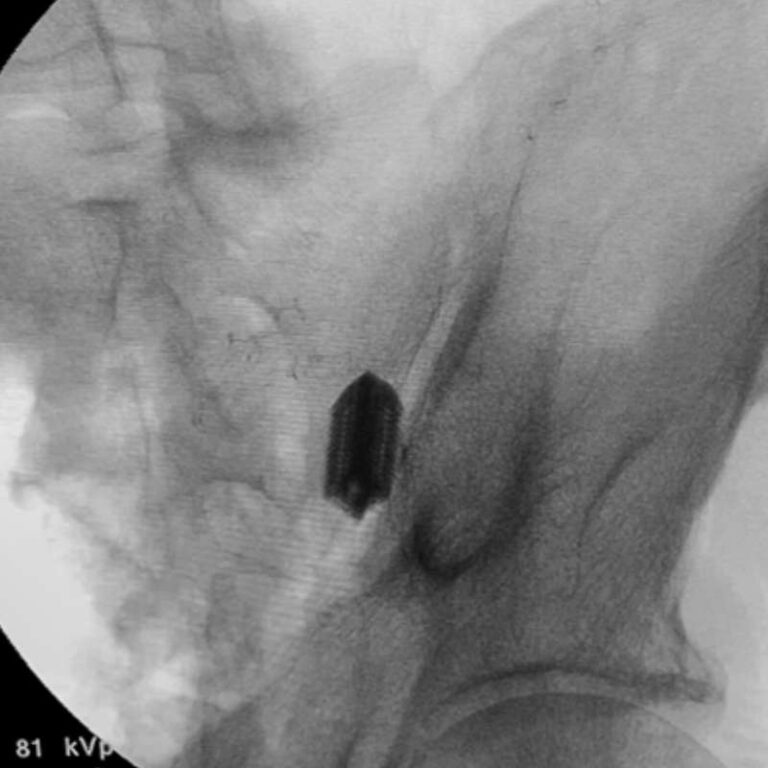

Step 1: Intra-Articular Implant Placement

Using fluoroscopic guidance, the porous intra-articular implant is inserted into the SI joint at the caudal apex to create an anchor point and ideal scaffold for biological fusion.